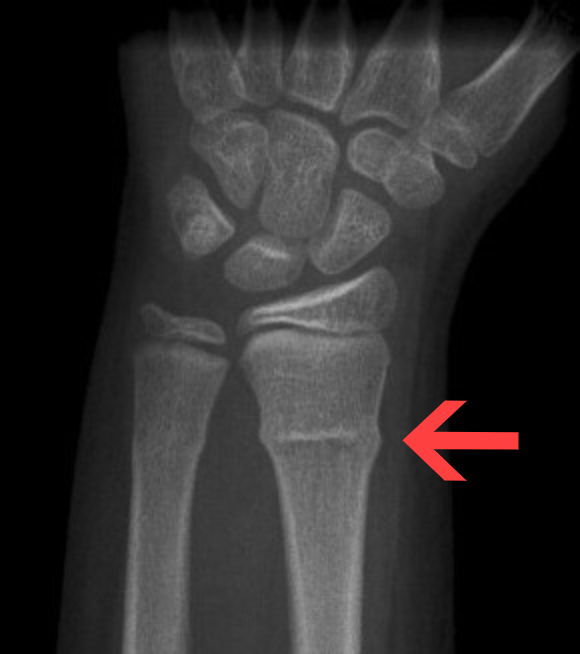

describe what the arrow is pointing at and how it occurs

torus/buckle fracture whereby compressive forces cause one side of bone cortex to buckle and bulge outward whereas the other side remains intact